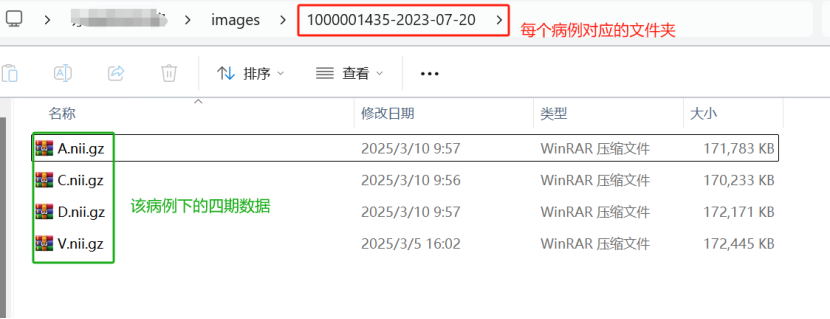

对于所有的每个病例数据,放在一个父文件夹下面,这里我放在images这个文件夹下:

每个病例下,必须四哥期的数据同时存在,且文件格式保持一致,即每例病人的四期对应的数据均以“.nii.gz”格式存在,如下图: